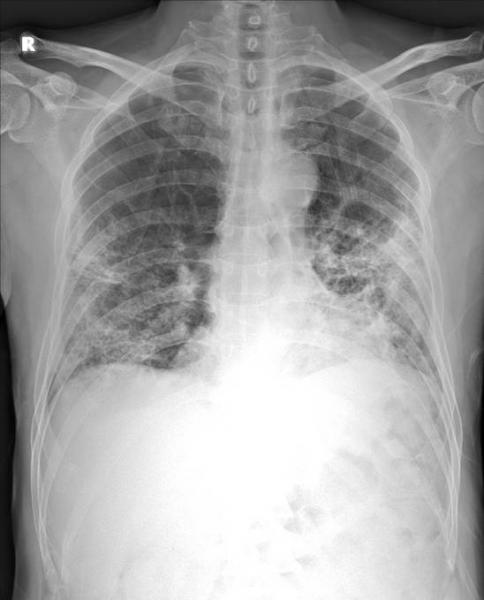

April 1, 2020 — Thirona and Delft Imaging launched CAD4COVID. This new artificial intelligence (AI) tool analyses X-ray images and is intended to support healthcare specialists manage COVID-19 cases. The companies have made the tool available free-of-charge in support of the crisis. Thirona and Delft Imaging are partnering with several hospitals and academic institutes worldwide to validate CAD4COVID.

Delft Imaging is specialised in tuberculosis (TB) screening and with its existing CAD4TB solution, which uses artificial intelligence to screen for TB. Over six million people have been screened in over 40 countries. Together with its sister company and AI-specialist Thirona, Delft Imaging developed a tool to help triage COVID-19 cases and indicate the affected lung tissue. CAD4COVID builds on the technical core of the CAD4TB software, developed and distributed by Thirona and Delft Imaging respectively. This software is used by Ministries of Health and tuberculosis-focused institutions, many of whom are now being tasked with helping to stop the spread of COVID-19 in their respective countries.

Preferred tools in the detection of COVID-19 are the RT-PCR test and the computed tomography (CT) scan, but in resource-constrained settings where the availability of such tools is limited and where COVID-19 is highly prevalent, X-ray can be a useful tool in the fight against COVID-19. In many countries, X-ray is currently used as a first-line triage before any further testing. Delft Imaging and Thirona have partnered with several academic institutes and hospitals in the Netherlands and abroad. These organisations will help with the development and validation of the software to support healthcare professionals in these times of crisis. The two Dutch companies aim to continuously improve the CAD4COVID software as more partners sign up.